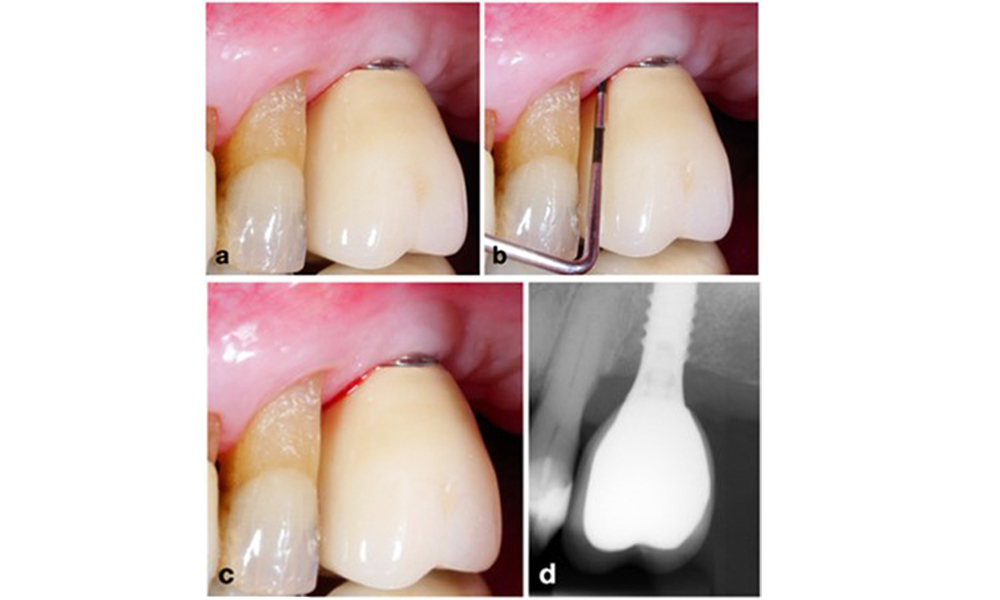

Implantat an Position 26 mit periimplantärer Mukositis (a-c). Die Sondierungstiefe von 5 mm (b) stimmt mit der wenige Wochen nach dem Einsetzen der prothetischen Rekonstruktion vorgenommenen Messung überein. Es kommt zwar zu einer Sondierungsblutung (c), aber die Röntgenaufnahme zeigt keinen weiteren Knochenverlust über das Maß hinaus, das bei einer marginalen Knochen-Remodellierung zu erwarten ist (d).

Abb. 1. Implantat an Position 26 mit periimplantärer Mukositis (a-c). Die Sondierungstiefe von 5 mm (b) stimmt mit der wenige Wochen nach dem Einsetzen der prothetischen Rekonstruktion vorgenommenen Messung überein. Es kommt zwar zu einer Sondierungsblutung (c), aber die Röntgenaufnahme zeigt keinen weiteren Knochenverlust über das Maß hinaus, das bei einer marginalen Knochen-Remodellierung zu erwarten ist (d).